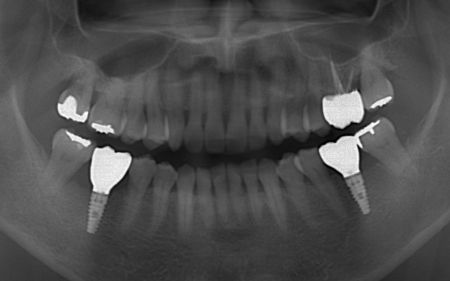

拝見したところ、上下左右の奥歯計8本(第1大臼歯、第2大臼歯)に重度の歯周病が認められました。

特に下の奥歯2本(左右第1大臼歯)は歯を支えている骨が著しく減少して歯が大きく揺れており、治療して温存することは難しい状態でした。

また、左上の奥歯(第1大臼歯)は過去に詰め物で治療されていましたが、その下で虫歯が再発しています。

以上のことから、下左右の第1大臼歯は抜歯後に歯を補う治療、その他奥歯の治療、再発した虫歯の治療が必要と診断しました。

診断結果を踏まえ、まず下左右の第1大臼歯については抜歯したあとにインプラントで補う方法を提案しました。

下左右の第1大臼歯を抜歯し、その部位にインプラントを埋め込む手術を行いました。同時に、インプラントの隣にある下の第2大臼歯に対して歯周組織再生療法を施しています。